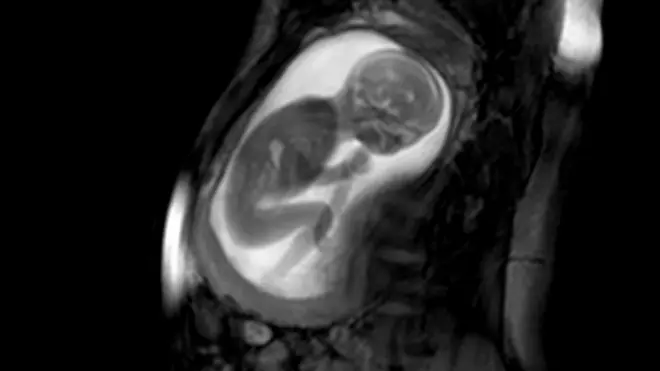

La cardiopatía congénita se refiere a problemas en la estructura y el funcionamiento del corazón por un desarrollo anormal del órgano antes del nacimiento.

Las cardiopatías congénitas son los defectos de nacimiento más comunes, con aproximadamente 1,35 millones de bebés afectados cada año, según un estudio global realizado por varias universidades entre 1970 y 2017.

Estas condiciones pueden aumentar la probabilidad de padecer una enfermedad cardiovascular en el futuro, incluso después de un tratamiento quirúrgico, y son la principal causa de muerte perinatal; es decir, la etapa inmediatamente anterior o posterior al nacimiento.